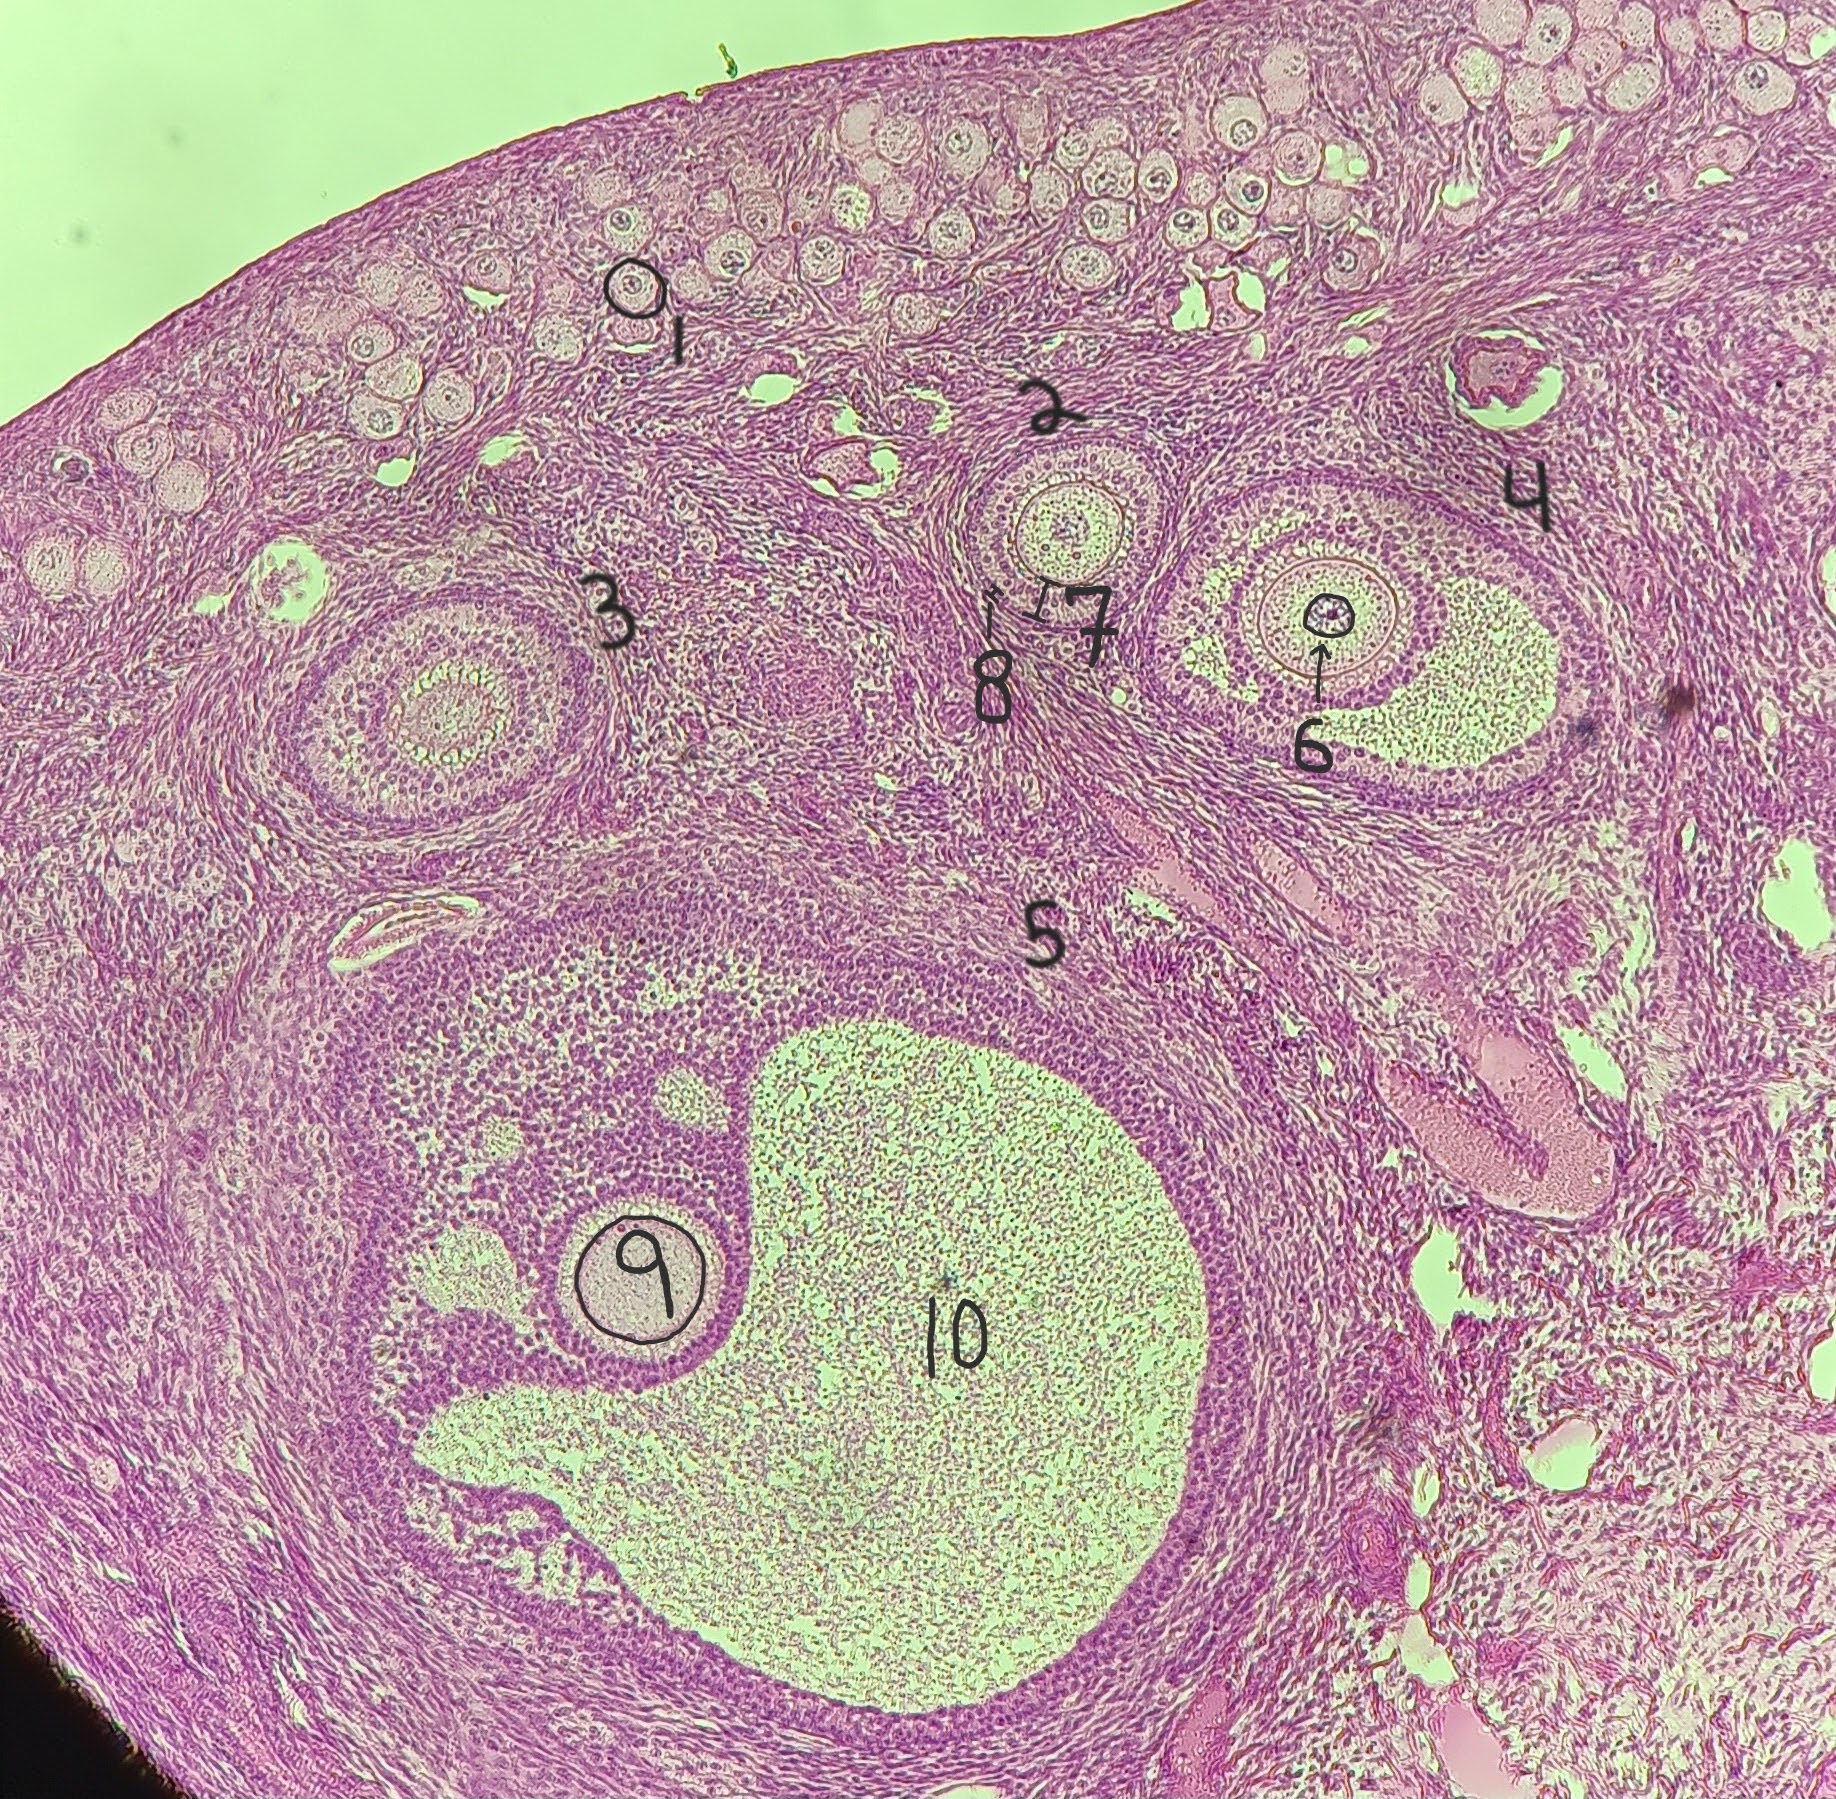

Primordial follicle

1

Primordial follicle

1

Primary follicle

2

2

Secondary follicle

3

3

Tertiary follicle

4

4

Mature follicle

5

Mature follicle

7

Antrum

10

Zona pellucida

9

Theca folliculi

8

corpus luteum

8

early corpus luteum

9

late corpus luteum

10